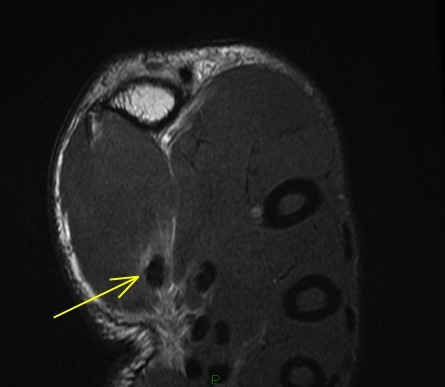

Figure 3 for case Flexor pollicis longus tendon ( RID2383 ) laceration

Figure 3